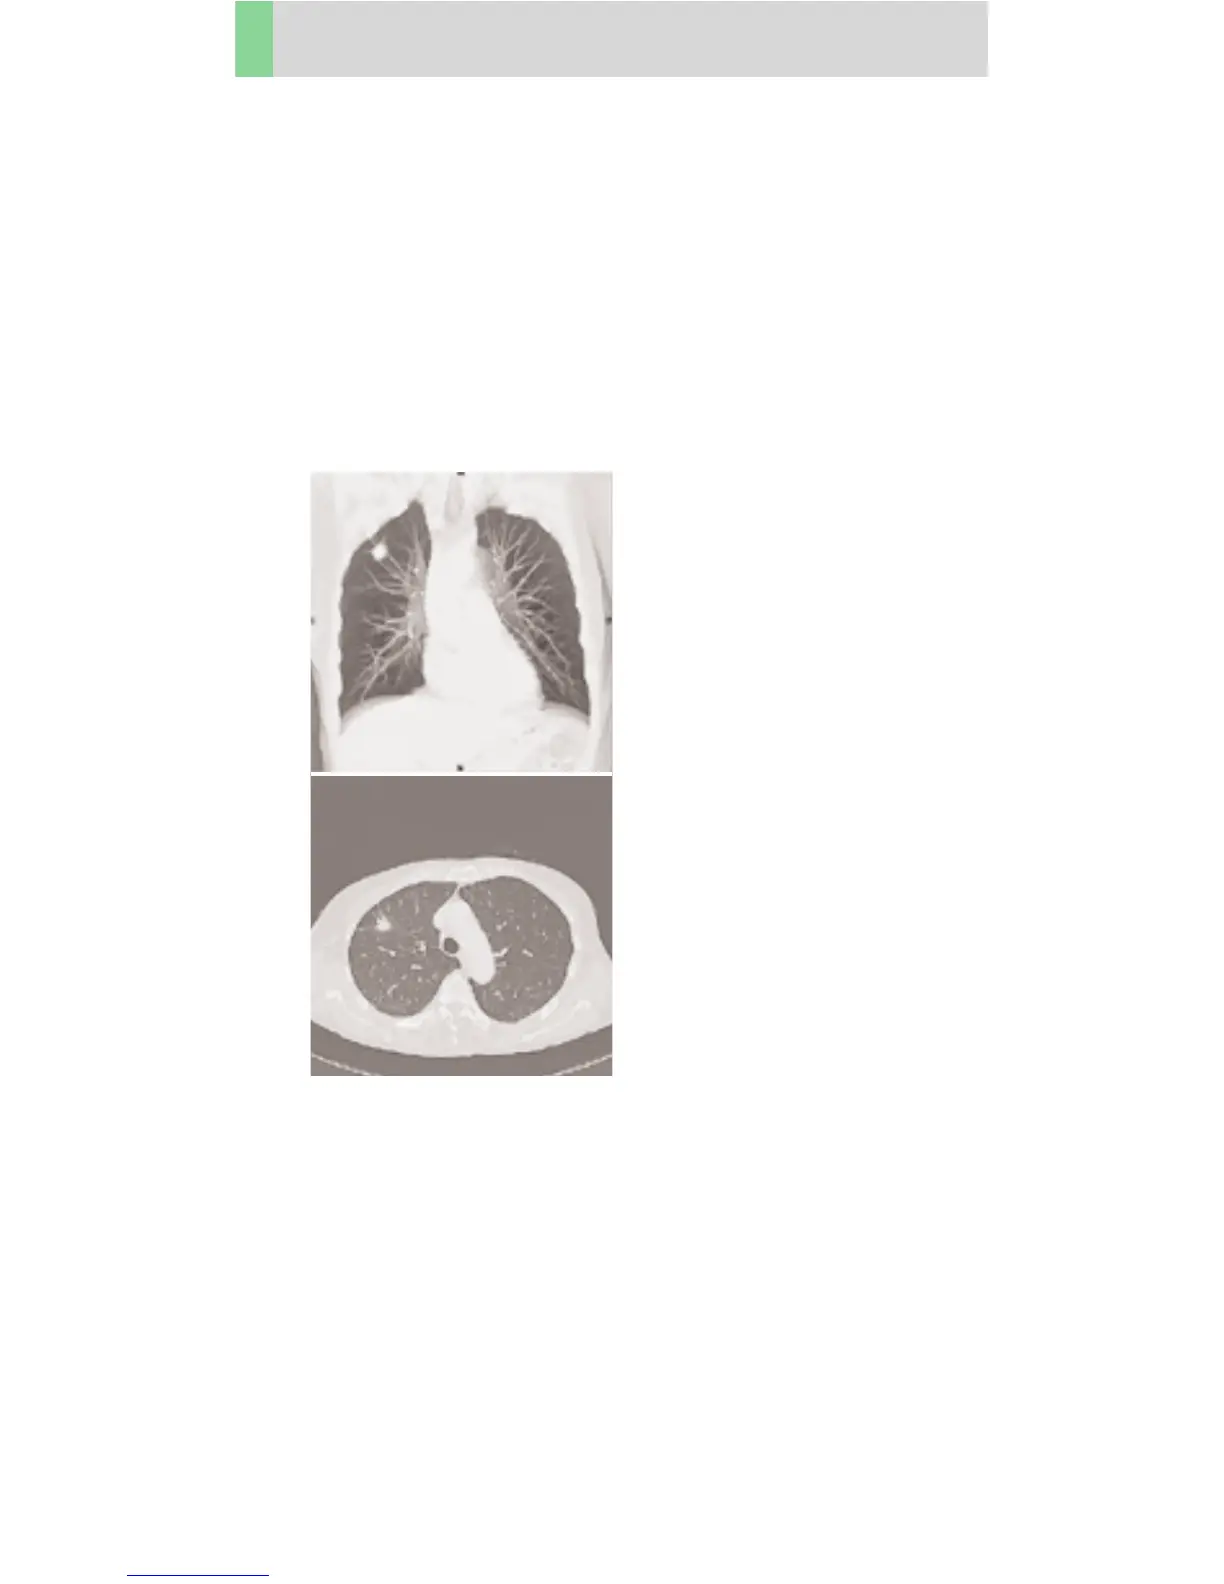

LungLowDose

Indications:

Lung studies with low dose setting, e. g. early visuali-

zation of pulmonary nodules.

A typical thorax study in a range of 30 cm will be

covered in 21.6 sec.